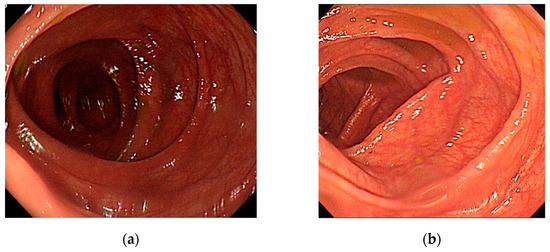

This section describes the image analysis methods used in this study, like this article [17]. The way we use computer programs to analyze textures has also been widely used in other areas [18]. The images are divided into three groups as previously described. Example images of patients with MC are illustrated in Figure 2a–c and the examples of regions of interest in Figure 2d–f.

Figure 2.

Images extracted from one patient with melanosis coli (a) cecum, (b) splenic flexure, and (c) colon polyp. The regions of interest (d) cecum—from (a); (e) splenic flexure—from (b); (f) colon polyp—from (c).

The images demonstrate that the MC has a particular dark brown pigmentation and presents a special black texture; places without pigmentation are white. The color textures of polyps or tumors are obviously different from the surroundings, exhibiting lighter and more turbulent textures, and most of them have no black texture.